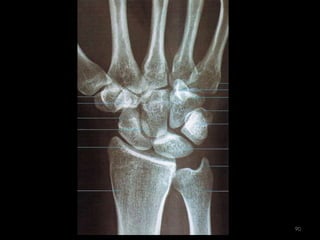

Incidência AP e PA do Punho88

89